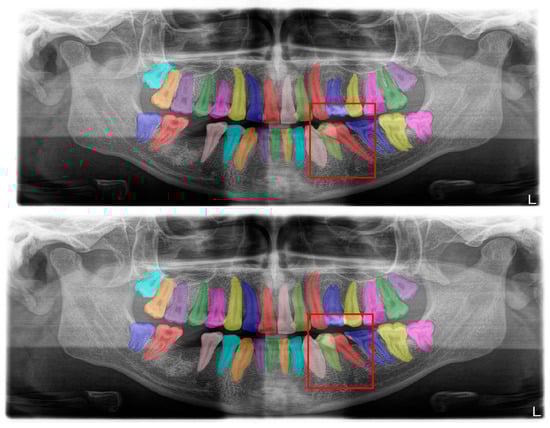

Figure 2.

Automatic segmentation of the teeth. Manual segmentation (upper image) and automatic segmentation (lower image) can be seen above. Each tooth has a unique label according to FDI World Dental Federation notation.